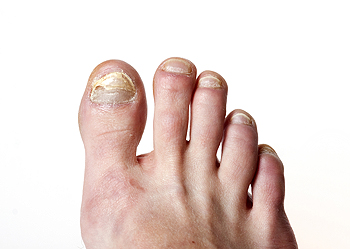

Thick toenails can develop for several reasons, and understanding the cause helps guide proper treatment. One of the most frequent reasons is a fungal infection, which can make the nail appear yellow, brittle, and difficult to trim. Repeated trauma from wearing tight shoes or stubbing the toe can also cause the nail to thicken as it tries to protect itself. Aging naturally slows nail growth and can change texture over time. In some cases, medical conditions such as psoriasis or poor circulation may contribute to nail thickening. A podiatrist can identify the cause through examination and testing, then recommend the right treatment, which may include antifungal medication, nail debridement, or improved footwear. If your toenails have become thick, painful, or hard to manage, it is suggested that you seek care from a podiatrist to restore nail health and prevent future problems.

If left untreated, toenail fungus may spread to other toenails, skin, or even fingernails. If you suspect you have toenail fungus it is important to seek treatment right away. For more information about treatment, contact Jeffrey Parrett, DPM of Parrett Podiatry. Our doctor can provide the care you need to keep you pain-free and on your feet.

Symptoms

- Warped or oddly shaped nails

- Yellowish nails

- Loose/separated nail

- Buildup of bits and pieces of nail fragments under the nail

- Brittle, broken, thickened nail

Treatment

If self-care strategies and over-the-counter medications does not help your fungus, your podiatrist may give you a prescription drug instead. Even if you find relief from your toenail fungus symptoms, you may experience a repeat infection in the future.

Prevention

In order to prevent getting toenail fungus in the future, you should always make sure to wash your feet with soap and water. After washing, it is important to dry your feet thoroughly especially in between the toes. When trimming your toenails, be sure to trim straight across instead of in a rounded shape. It is crucial not to cover up discolored nails with nail polish because that will prevent your nail from being able to “breathe”.

In some cases, surgical procedure may be needed to remove the toenail fungus. Consult with your podiatrist about the best treatment options for your case of toenail fungus.